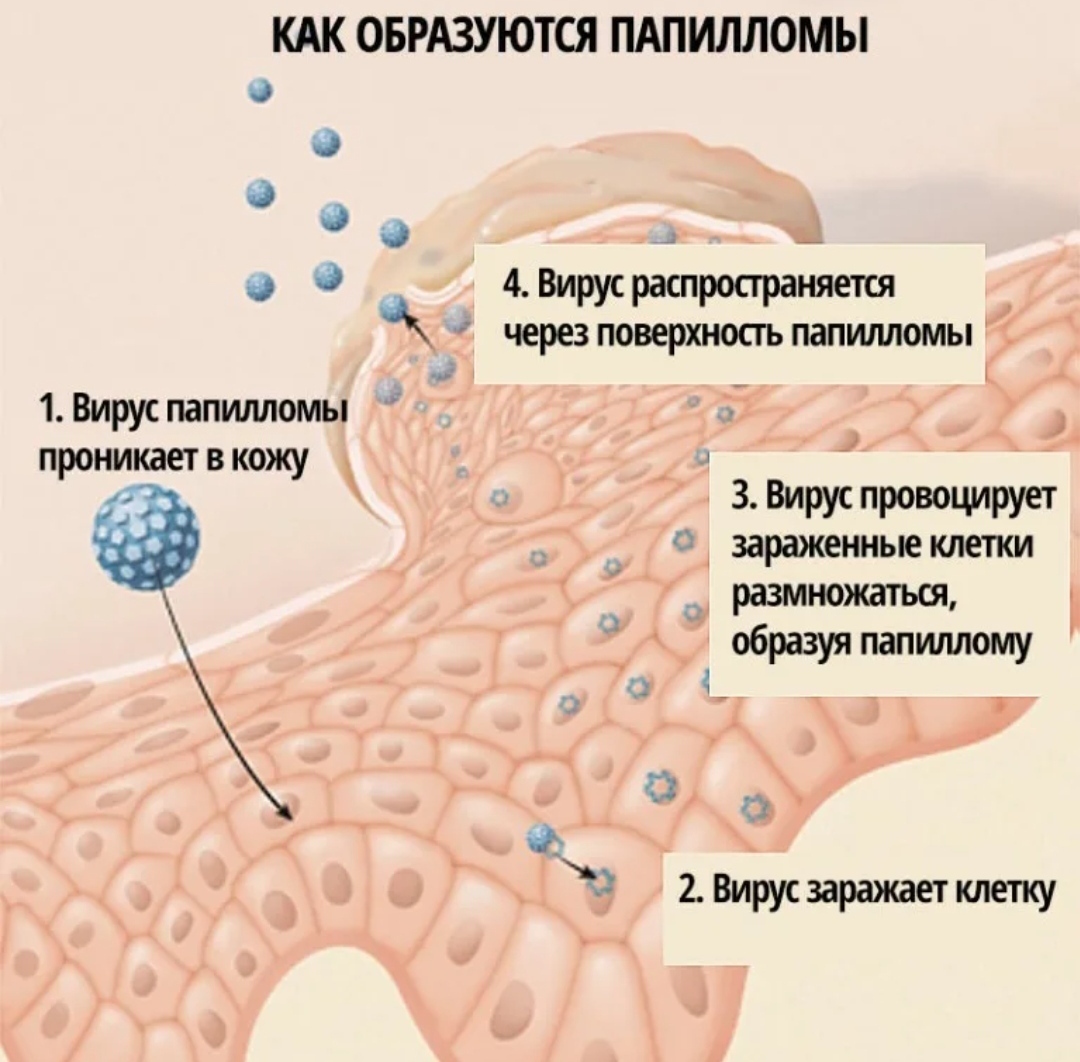

Кондиломы - это одно из самых распространенных заболеваний, передающихся половым путем. Они вызваны вирусом папилломы человека (ВПЧ) и могут появляться на внешних половых органах, анусе, ротовой полости и других областях тела.

Симптомы кондилом могут варьироваться, и визуальное представление этого заболевания может быть различным. Некоторые кондиломы выглядят как небольшие бугорки или бородавки, в то время как другие могут иметь форму плоских пятен или цветных наростов.